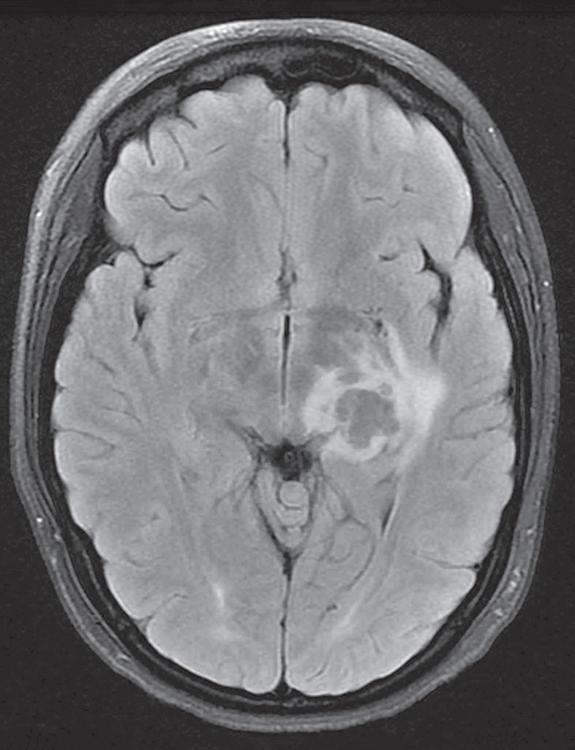

1.2 This 16-year-old girl presented to the ophthalmology department complaining of headaches, blurred vision in her right eye and flashing lights. Visual acuity was 20/20 in each eye and intraocular examination was normal. No visual field testing was performed, and the patient was told her symptoms were due to migraine. Re-examination by another doctor revealed a right homonymous hemianopia (A, B) that was easily detected with confrontation testing; C a left thalamic mass lesion was diagnosed on MRI; further investigation showed this to be a cryptococcal abscess.

Blurred vision or field loss